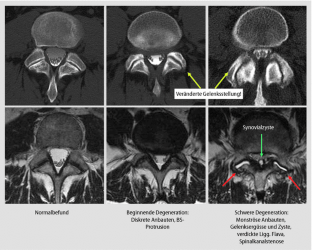

Abb. 2